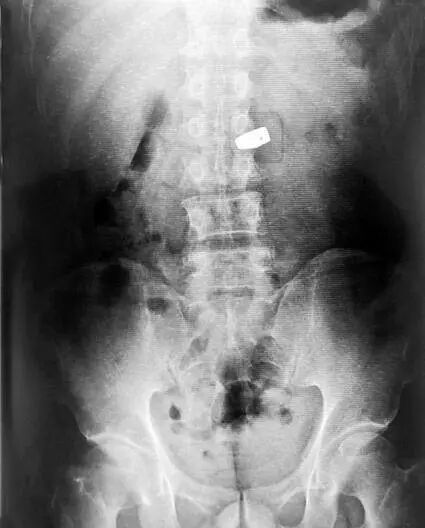

一名中国女游客秦某,在泰国曼谷珠宝展上趁人不备,把一颗价值200万人民币的6克拉钻石囫囵吞下。警方通过X光,找到位于其大肠中的钻石,并让医生使用肠镜等器械,将钻石从该女子的肠中取出。人赃并获时,女子竟然用日语对警察道歉说“おわび申し上げます”(我对此非常抱歉)。

事后,警察在检查护照时发现,该女子确系中国人。但是,值得注意的是,失窃的珠宝商也被一同抓了起来,因为涉嫌高价贩卖假钻——据悉,真钻在X光下是无法被发现的。

▲真钻在X光下是无法被发现的